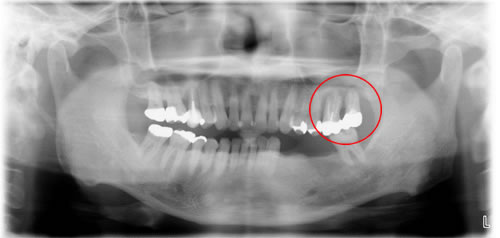

初診時

赤丸の部位が歯周病で歯が抜け落ちそうです。重度の歯周病によって、歯槽骨が吸収していくと、骨の幅や高さが減少していきます